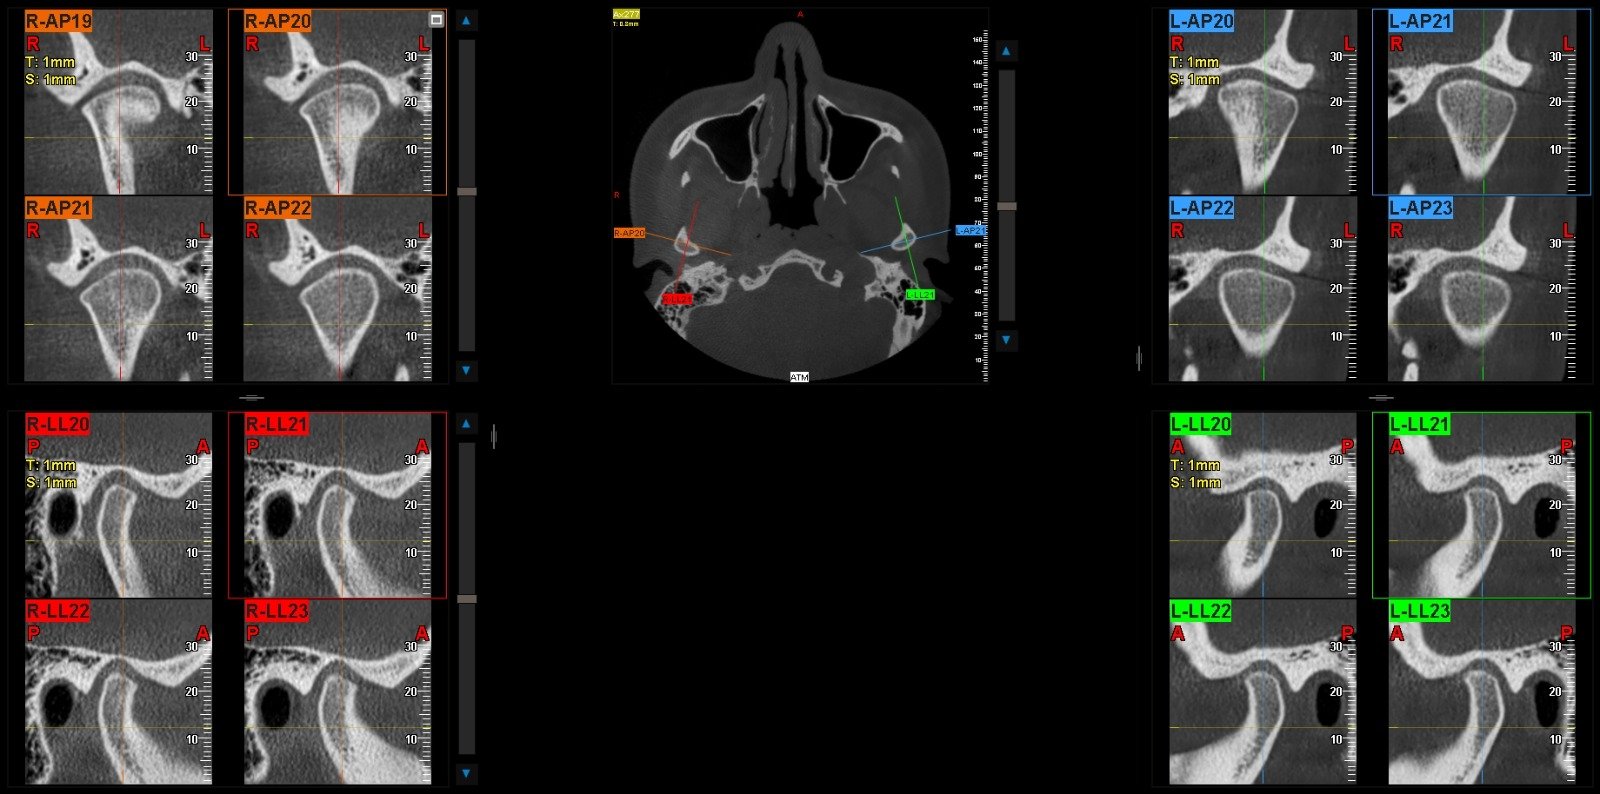

Los problemas en la región maxilofacial no solo afectan la boca. Pueden influir en la manera de hablar, comer, respirar e incluso dormir. Una maloclusión severa, por ejemplo, puede generar dolor crónico en las articulaciones temporomandibulares (ATM), dolores de cabeza y dificultad para masticar. Un TAC macizofacial puede identificar la causa subyacente de estos problemas al visualizar las articulaciones y las estructuras óseas circundantes, sentando las bases para su tratamiento y, por ende, mejorando la calidad de vida del paciente. Imaginen lo que significa comer sin dolor, o dormir sin apneas.

Anormalidades de las Articulaciones Temporomandibulares (ATM)

Las ATM son las articulaciones que conectan la mandíbula al cráneo, y sus disfunciones pueden causar dolor, chasquidos, limitación de la apertura bucal y dolores de cabeza. Un TAC macizofacial proporciona una vista detallada de la anatomía ósea de las ATM, permitiendo detectar artrosis, erosiones óseas, anquilosis o desplazamientos del cóndilo mandibular, lo que es esencial para un diagnóstico y tratamiento efectivos de las disfunciones temporomandibulares.

Numerosos casos clínicos ilustran la importancia del TAC macizofacial. Por ejemplo, un paciente con dolor facial inespecífico, donde las radiografías convencionales no revelaban nada, pudo obtener un diagnóstico de sinusitis maxilar crónica oculta gracias a un TAOtro ejemplo es la planificación de implantes en pacientes con poco hueso, donde el TAC permite identificar las zonas con suficiente densidad ósea y evitar estructuras nerviosas o sinusales, asegurando el éxito del tratamiento. En la detección de pequeños tumores ocultos, el TAC ha sido crucial para su identificación temprana, permitiendo una intervención oportuna y salvando la vida del paciente.